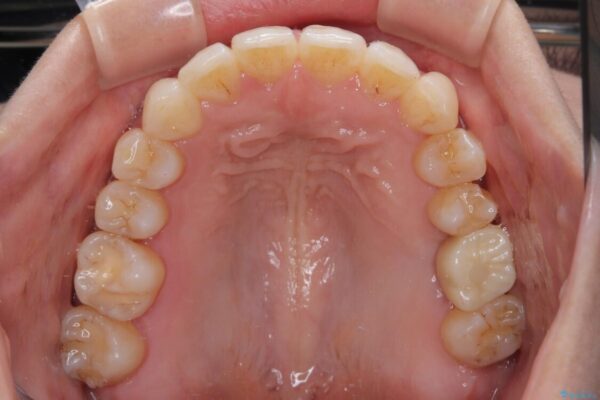

治療後について

歯の傾斜が改善され、インプラントによるクラウンが装着されたことで、物が挟まることもなくなりました。

治療後

• インビザラインによる矯正治療と奥歯のインプラント治療 治療後画像